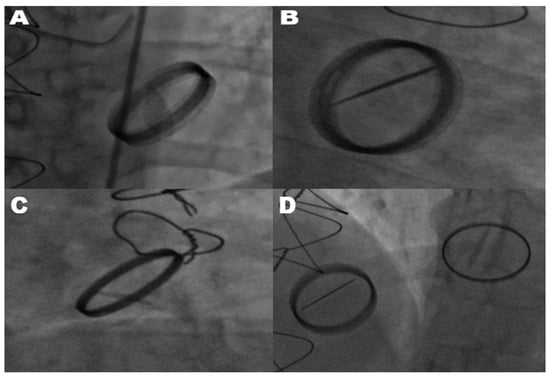

The diagnosis of mechanical prosthetic valve dysfunction, specifically a stuck valve, was confirmed through the combined use of transthoracic echocardiography and fluoroscopy. Transthoracic echocardiography was employed as the primary modality to evaluate leaflet mobility, detect the presence of thrombus or pannus, and assess associated hemodynamic alterations. Fluoroscopy complemented echocardiographic findings by directly visualizing the mechanical motion of valve leaflets. In cases where only one leaflet demonstrated motion, fluoroscopy reliably identified restricted leaflet mobility, confirming a stuck valve diagnosis. Echocardiography and fluoroscopy, when used in tandem, significantly improved the diagnostic accuracy of stuck valve identification and minimized the risk of misdiagnosis. This two-tiered assessment approach ensured the reliability of the diagnosis, enabling clinicians to proceed with surgical intervention despite the elevated operative risks associated with reoperation. All mechanical valves included in this study were bileaflet prosthetic valves, as verified through surgical and echocardiographic records. This uniformity in valve type minimized the variability stemming from differences in valve design, ensuring the study’s focus on pannus formation and hemodynamic gradients remained consistent. As shown in Figure 1, fluoroscopic imaging highlights the hallmark feature of limited leaflet motion in bileaflet metallic valves. This restriction in leaflet mobility significantly impairs hemodynamic function and was observed across various valve positions, including the mitral, aortic, and tricuspid valves.

Figure 1. Fluoroscopic images of restricted leaflet movement in stuck prosthetic valves. This figure shows a fluoroscopic assessment of restricted leaflet movement in stuck metallic bileaflet mitral, aortic, and tricuspid valves, likely due to the mechanical obstruction caused by pannus. (A) Shows the mitral valve in a partially open position, with only one leaflet exhibiting movement, indicating a significant obstruction affecting valve function. (B) Depicts the mitral valve in an open position, with one leaflet remaining immobile, further demonstrating a mechanical limitation likely due to pannus. (C) Illustrates a stuck bileaflet metallic aortic valve, where the restricted leaflet movement suggests interference at the valve plane. (D) Displays a patient with previous metallic bileaflet mitral valve replacement and tricuspid valve replacement. In this view, only one leaflet of the stuck tricuspid valve is moving, highlighting that there is also an obstruction in the tricuspid valve. Additionally, the metallic bileaflet mitral valve is functioning normally, with both leaflets opening fully.